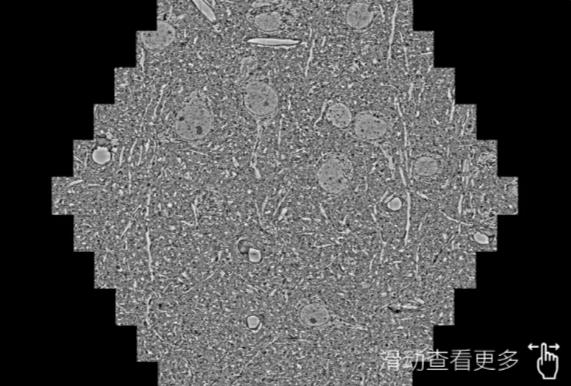

鼠脑切片。左图使用保定蔡司保定扫描电镜MultiSEM706对165μmx143pm面积区域成像,耗时仅需1.5秒。右图为鼠脑切片中30μm区域放大效果。样品由芝加哥大学B.Kasthuri提供。

使用蔡司高速保定扫描电镜MultiSEM对1mm²人脑皮层组织进行高分辨成像,并对其中的各种细胞结构进行三维重构分析。左图展示了2x3mm²组织平面中锥体神经元的三维重构效果。右图显示了局部体积神经元三维重构。图像由哈佛大学chtman实验室提供,渲染图由D. Berger 制作。